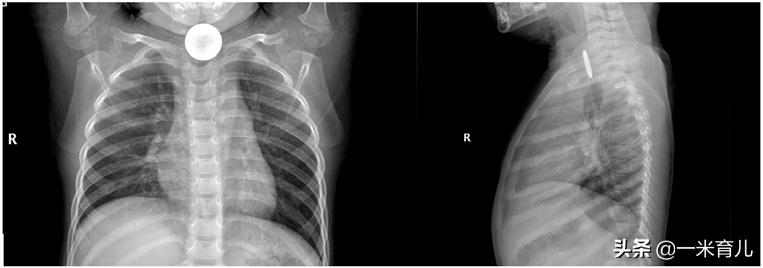

- 纽扣电池变老虎?

越来越多的玩具、家用电器中使用纽扣电池。据统计,儿童吞食纽扣电池的发生率约为 6/1000000~15/1000000。

因纽扣电池含有重金属及化学复合物,对食道壁具有较强的腐蚀性,儿童吞食纽扣电池后,能对食管造成阻塞和碱性化学物质烧伤,极易导致食管穿孔、气管食管瘘、大出血、食管狭窄等严重并发症。

一旦发生儿童误食纽扣电池,应尽快送医院诊治,制定适宜的治疗方案对孩子的预后十分重要。

有些直径较小的纽扣电池可通过胃肠道,几天后随粪便排出体外;但如果电池直径超过20毫米,则可能会嵌顿在食道中,需要快速诊断和迅速取出。

儿童吞食纽扣电池临床特征

纽扣电池食管异物已成为全球性问题,每一个家庭都应该做好对纽扣电池的管理,与孩子一起了解纽扣电池的危害,预防意外情况的发生。